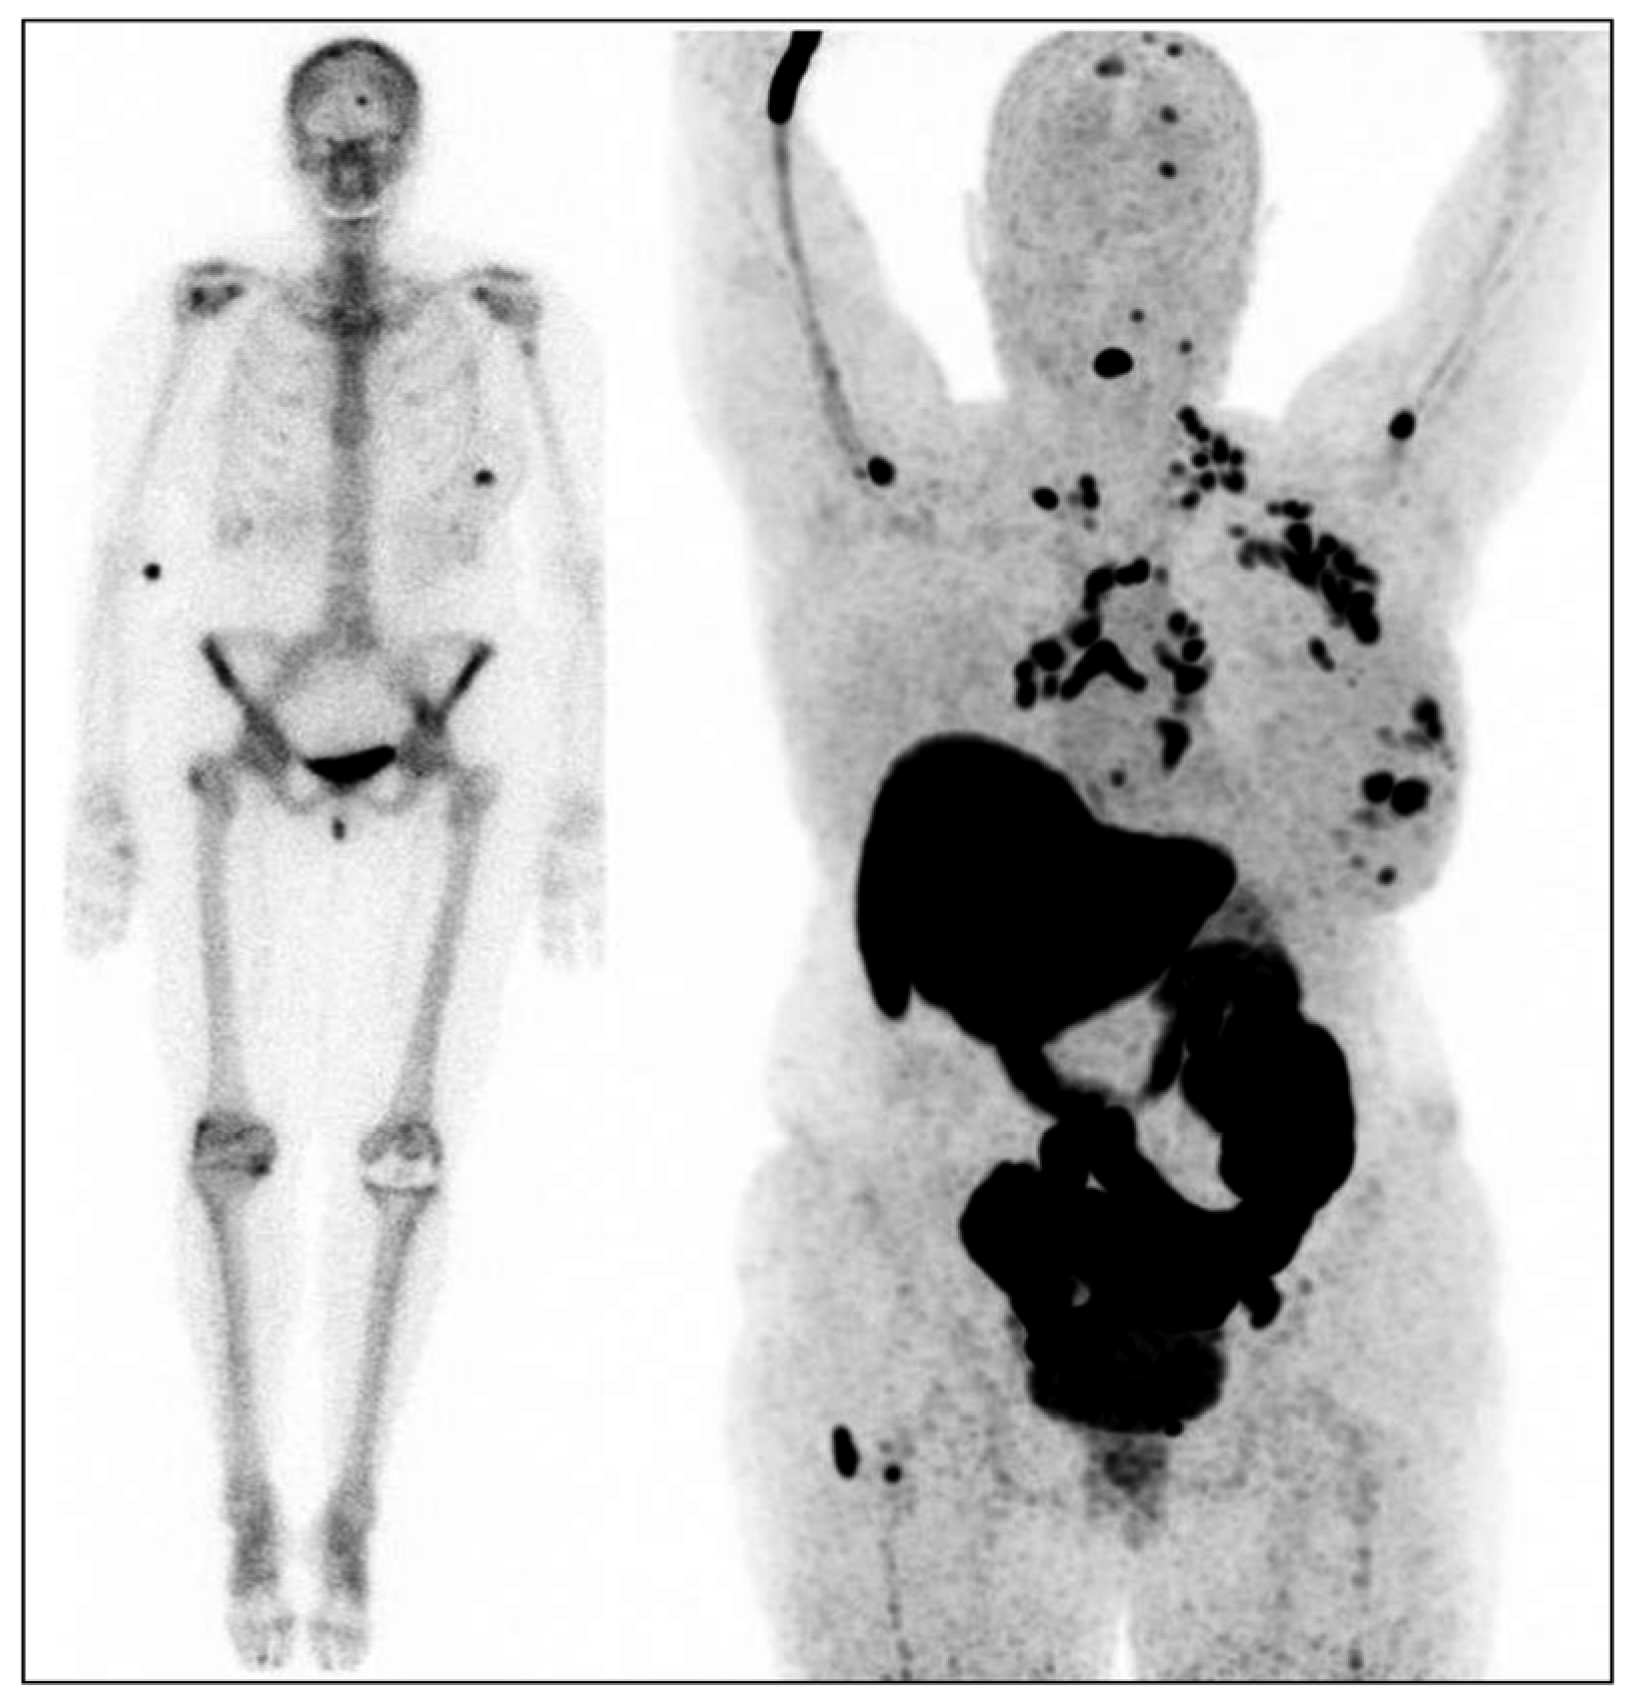

:1. Introduction

3. Discussion